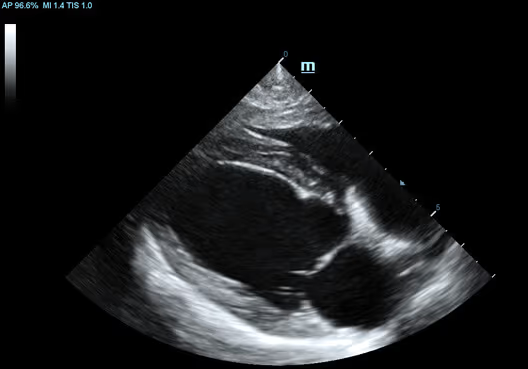

Uzun Eksen, Kalp, Köpek

Uzun Eksen, Kalp, Köpek